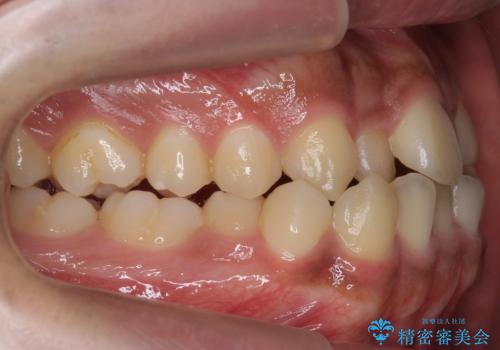

骨格性の受け口 非抜歯で下の歯を後ろに下げる インビザラインで インプラント矯正

- 受け口を主訴に来院。

他院でマウスピース矯正を始めたが、担当医に不信感をもち転院。

治療により受け口が改善し、下あごの輪郭も若干後ろに下がった印象になりました。

当院では下の歯を後ろに下げるため矯正用ミニスクリューを用いてしっかり移動を行う等ご説明をし、治療開始しました。